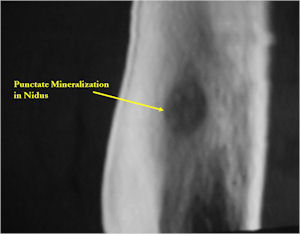

CT Scan:

- Well defined nidus with a smooth peripheral margin; +/- mineralization (CT more sensitive than XR and MRI for detecting mineralization); CT is better for detecting nidus in presence of exuberant sclerosis

- Lucent nidus surrounded by a zone of marked sclerosis

- The nidus may demonstrate mineralization/ossification usually from the center outward that appears as a central zone of density within the nidus

- A nidus that is heavily ossified may blend in with the surrounding sclerosis and be difficult to detect on a plain x-ray.